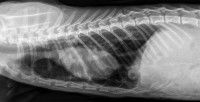

Puis, après l'avoir ausculté, le vétérinaire effectue une radiographie de ses poumons. Cela permet de mettre en évidence des anomalies dans les poumons : si le chat est effectivement atteint d’une pneumonie, une ou plusieurs opacités (des zones blanches sur la partie normalement noire du poumon) sont alors visibles sur la radiographie. Le vétérinaire est alors en mesure de préciser la gravité de l’infection et l'état des poumons.

Dans tous les cas de figure, si la pneumonie est prise en charge à temps, l'animal voit son état de santé s'améliorer rapidement, et se sent mieux en quelques jours. Malgré tout, les médicaments doivent continuer à être administrés jusqu'à la guérison totale, ce qui peut prendre plusieurs semaines voire mois, selon la gravité et l'origine de l’infection. A la fin du traitement, le vétérinaire effectue une radio de contrôle pour confirmer la guérison totale.